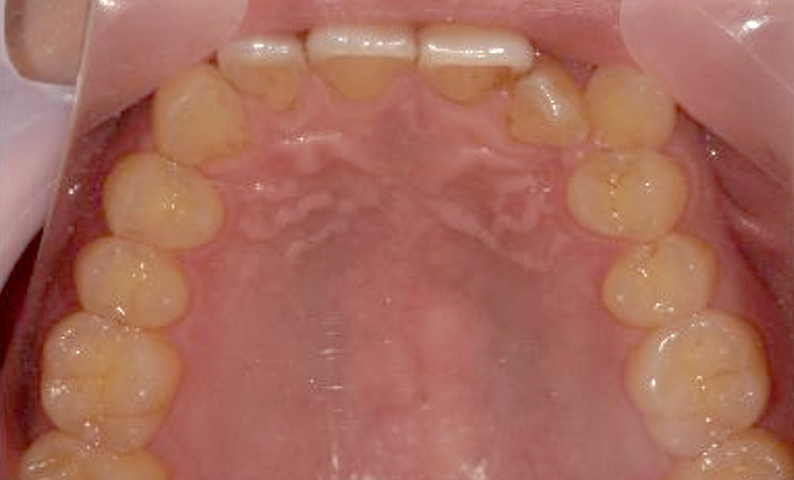

症例_002 上顎だけの部分矯正

治療期間:7ヶ月金額:30万円+税女性前歯のガタガタ上の前歯だけ

| Before | After |

|---|---|

|